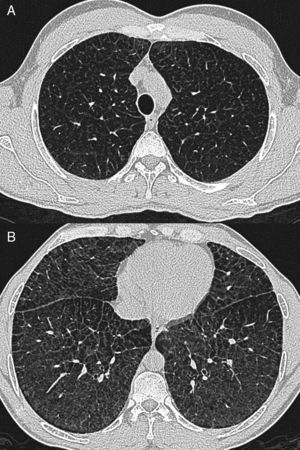

Caso clínicoPaciente varón de 40 años, diagnosticado de enfermedad de N-P con afectación hepática y pulmonar. Antecedentes personales: hepatoesplenomegalia diagnosticada desde los 6-7 meses de vida. Ingresa a los 6 años de edad por cuadro de astenia, anorexia, decaimiento y fiebre. Se le realizó radiografía de tórax posteroanterior y lateral (PA-L), en la que se apreció un patrón reticular difuso. Ante los hallazgos radiográficos y la presencia de hepatoesplenomegalia se sospechó enfermedad por depósito, realizándose biopsia de la mucosa rectal y biopsia hepática, que fueron sugestivas de enfermedad de N-P (se visualizaron macrófagos cargados de lípidos). La exploración neurológica y las pruebas de función respiratoria fueron normales. Se confirmó el diagnóstico a los 20 años mediante biopsia de piel con cultivo de fibroblastos, comprobándose un marcado déficit de actividad de esfingomielinasa ácida (ASM) característica de enfermedad N-P que, apoyando el diagnóstico clínico, sería tipo B. A los 38 años se realizó el diagnóstico molecular, en el que se observaron dos mutaciones en el gen SMPD (presentó heterocigosis en mutación p.R608del). Actualmente sigue revisiones en consultas de neumología y en consultas de hepatología, y presenta ictericia intermitente y disnea de máximos esfuerzos (grado 0 MRC). En la exploración física destaca la presencia de mínimos crepitantes bibasales, ictericia subconjuntival y hepatoesplenomegalia. La exploración neurológica es normal. En la analítica los resultados más destacables son: bilirrubina total, 4,17mg/dl; GOT, 38UI/l; GPT, 45UI/l; colesterol total, 221mg/dl. Las pruebas de función respiratoria muestran un patrón ventilatorio normal (FVC,3,84 [87,7%]; FEV1, 3,13 [86%]; FEV1/FVC, 81,58%; TLC, 5,26 [81,8%]) y una alteración leve del intercambio gaseoso (DLCO, 57,5%). Hallazgos radiográficos: radiografía PA-L de tórax (fig. 1 A-B): en el parénquima pulmonar se observa una afectación intersticial reticular difusa de predominio en campos medios e inferiores; TCAR (Aquilion Toshiba de 64 detectores) (fig. 2 A y B): afectación en vidrio deslustrado difusa aunque de predominio en los lóbulos inferiores con engrosamientos septales subpleurales en la pleura periférica, mediastínica y cisuras. No se observan adenopatías mediastínicas ni hiliares. El paciente actualmente no sigue ningún tratamiento y únicamente presenta afectación hepática y pulmonar sin que haya afectación del sistema nervioso central.

El tipo B no parece tener predilección por el sexo y se manifiesta a cualquier edad, aunque es más frecuente antes de los 20 años7. Existe una afectación crónica visceral que se desarrolla de forma lenta2 y presenta una amplia variabilidad en la severidad de los síntomas y los hallazgos clínicos3. La hepatoesplenomegalia es bastante común, con crecimiento esplénico sobre todo1. Se afectan las pruebas de función hepática con aumento de transaminasas y bilirrubina. Puede aparecer trombocitopenia, que podría ser secundaria a infiltración de la médula ósea por células de N-P8, y también puede producir leucopenia. La enfermedad pulmonar es frecuente, y en la mayoría de pacientes aparecen alteraciones en la radiografía o la TACAR de tórax1. La incidencia exacta de la afectación pulmonar es difícil de determinar, pero es raro en adultos y más común en las formas infantiles9. Las células de N-P se acumulan en los septos alveolares, en las paredes bronquiales y en pleura y ocasionan un patrón restrictivo que empeora progresivamente, pudiendo llegar a fallo respiratorio1 con dependencia de oxígeno y/o reducción de la tolerancia al ejercicio físico10. Las pruebas de función respiratoria muestran dicho patrón restrictivo con incapacidad para el intercambio gaseoso, y la ergometría cíclica es anormal en la mitad de los pacientes3. Los hallazgos radiológicos vienen determinados por la existencia de un patrón reticulonodular con engrosamiento de septos interlobulares, opacidades en vidrio deslustrado y a veces nódulos subcentimétricos que pueden estar calcificados2,8,10. En ocasiones la combinación de estos hallazgos produce la imagen llamada crazy paving en TACAR, si bien estos hallazgos no son específicos. El diagnóstico diferencial de este patrón incluye: edema pulmonar, hemorragia pulmonar, linfangitis, proteinosis alveolar, amiloidosis3 y neumonía intersticial no específica. Sin embargo, la asociación con hepatoesplenomegalia debería sugerir enfermedad por depósito2. Existe una pobre correlación entre los test de función pulmonar y los hallazgos morfológicos en la TACAR, lo que implica que los cambios intersticiales no siempre afectan al intercambio gaseoso en un grado significativo3,10. Por lo tanto, la presencia de enfermedad pulmonar intersticial en la radiografía simple o en la TACAR no es necesariamente un indicador fiable de aparición de síntomas clínicos ni de la alteración de las pruebas funcionales respiratorias. Para el estudio de las alteraciones pulmonares en esta enfermedad deben emplearse tanto la radiografía simple de tórax como la TACAR1. En nuestro caso, la afectación pulmonar se evidenció a los 6 años mediante la detección de patrón reticular en la radiografía simple de tórax, pero el paciente no ha presentado hasta el momento actual clínica respiratoria significativa.

Nuestro caso presenta la mayoría de los hallazgos pulmonares radiológicos descritos en la literatura con presencia de crazy paving con gradiente ápico-basal. Las pruebas de función respiratoria que presenta no se correlacionan con las alteraciones morfológicas en la TCAR, puesto que los test respiratorios son prácticamente normales. Por tanto, creemos que aunque la enfermedad de N-P es una entidad rara que presenta unas alteraciones radiológicas inespecíficas, éstas pueden apoyar el diagnóstico inicial y su confirmación. Ante un trastorno de almacenamiento de lípidos o una enfermedad de depósito habría que tener siempre en cuenta la afectación pulmonar, y la técnica radiológica más fiable es la TACAR5. Aunque el patrón en crazy paving no es el más específico para este tipo de enfermedad, esta debería estar incluida en su diagnóstico diferencial de acuerdo con lo expresado anteriormente en la literatura5,10.